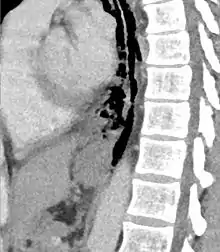

Axial CT image through the upper chest showing extraluminal air (Pneumomediastinum) surrounding the trachea and esophagus

Sagittal reformatted CT image showing discontinutity in the wall of the posterolateral aspect of the distal esophagus

The diagnosis of Boerhaave's syndrome is suggested on the plain chest radiography and confirmed by chest CT scan. The initial plain chest radiograph is almost always abnormal in patients with Boerhaave's syndrome and usually reveals mediastinal or free peritoneal air as the initial radiologic manifestation. With cervical esophageal perforations, plain films of the neck show air in the soft tissues of the prevertebral space.

Hours to days later, pleural effusion(s) with or without pneumothorax, widened mediastinum, and subcutaneous emphysema is typically seen. CT scan may show esophageal wall edema and thickening, extraesophageal air, periesophageal fluid with or without gas bubbles, mediastinal widening, and air and fluid in the pleural spaces, retroperitoneum or lesser sac.